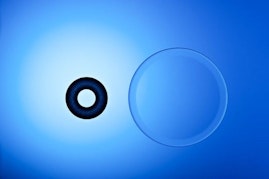

Tired of Glasses and Contacts?

Have you grown weary of the hassle and expense associated with glasses and contact lenses? Safe, effective and nearly painless procedures are available to sharpen vision and do away with the need for cumbersome visual aids. At Sheth-Horsley Eye Center, our specialists perform a range of refractive surgeries to improve our patients' eyesight. If you are interested in learning more or would like to schedule an examination with Dr. Nilesh M. Sheth or Dr. Robert Kupsc, please take the time to fill out our simple online contact form.